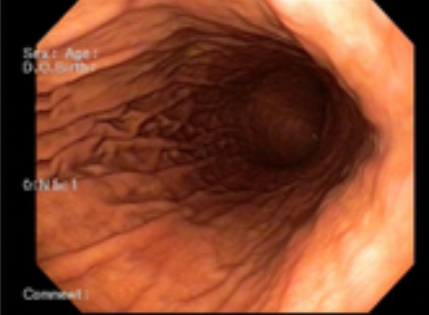

위내시경 검사 금식시간은 병원이나 방법에 따라 차이가 있을 수 있습니다. 위 안으로 내시경 카메라를 삽입해 식도와 위를 봐야 하기 때문에 음식물이 남아있으면 정확하게 검사하기가 어렵습니다.

위내시경 금식시간은 검사받는 시간 기준 최소 8시간은 아무 음식도 먹지 않고 금식해야 정확한 진단이 가능합니다. 미음이나 흰 죽 같은 유동식 음식을 드실 경우 위내시경 금식시간은 6시간 정도 지켜주면 됩니다. 보통 오전에 위내시경을 한다면 검사 전날인 저녁 8시 이후로는 음식 섭취를 제한하고 금식해야 합니다.

위내시경 검사받기 4시간 전에는 물(커피, 주스, 이온음료, 사탕 등)도 먹지 않는 것이 좋습니다. 참고로 껌은 먹다가 삼키는 것이 아니기 때문에 괜찮다는 의견이 있지만 일부 전문의는 금식해야 한다는 의견이 있으므로 피하는 것을 권장드립니다.

위내시경 검사를 앞두고 있다면 전날 식사에도 신경 써야 합니다. 짜거나 기름진 육류 위주 음식, 맵거나 자극적인 음식, 소화가 잘 안 되는 밀가루 음식은 피해야 하며, 흰 죽 같은 소화가 잘 되는 부드러운 음식을 먹는 것이 좋습니다.

특히 소주의 경우 위 점막을 자극해서 검사할 때 출혈이 발생할 수 있으므로 반드시 금주하기시 바랍니다. 특히 흡연의 경우 위 운동을 자극시켜 위액 분비를 촉진시킬 수 있어 검사에 방해가 되고, 불편감을 초래할 수 있기 때문에 반드시 금연하는 것이 좋습니다.